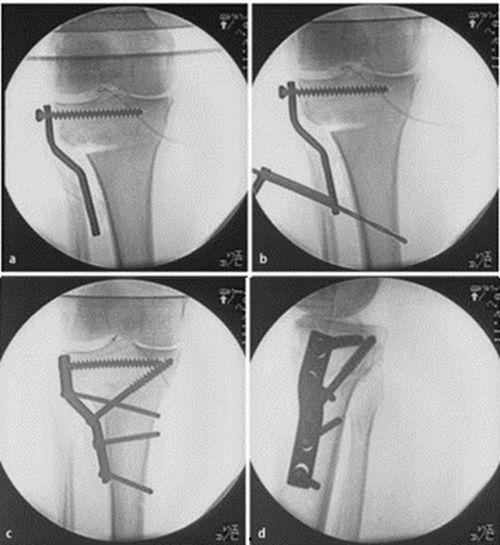

3. 内固定

截骨完成后,医生会在胫骨上安装内固定装置,以保持截骨部位稳定。常见的内固定装置有钢板、螺丝和髓内钉等。这些装置会在手术过程中被植入患者的骨骼中。